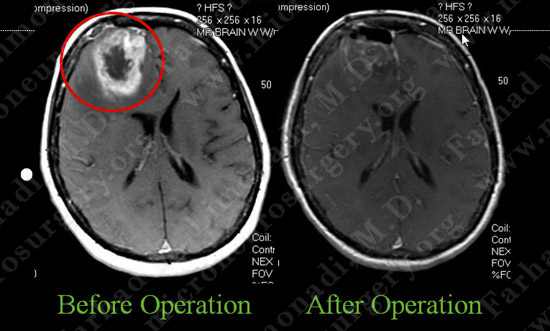

Post-op Imaging

Post-op MRI shows complete resection of the tumor with no injury to surrounding neurovascular structures.